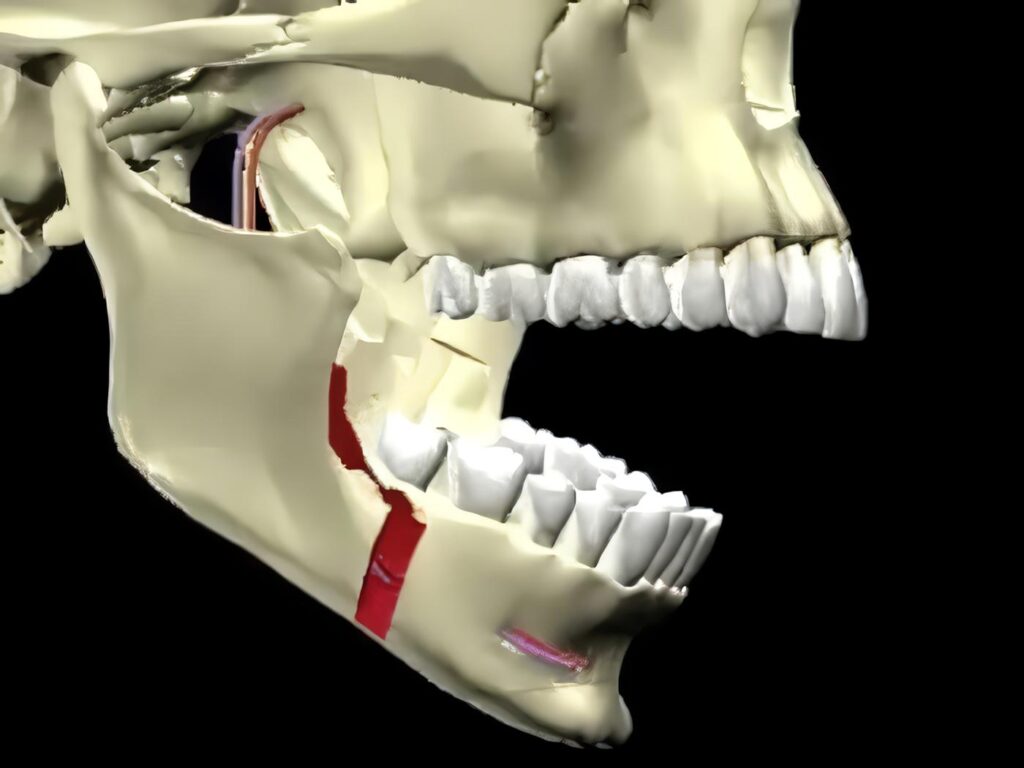

Osteotomía Sagital para Alargamiento del Mentón

Doctor: LUIS A. CAMPOS* Profesor Universidad Nacional; Universidad Javeriana. Bogotá Jefe Servicio Cirugía Maxilofacial, C.S.P.C.; C.M.A. Summary The chin is...